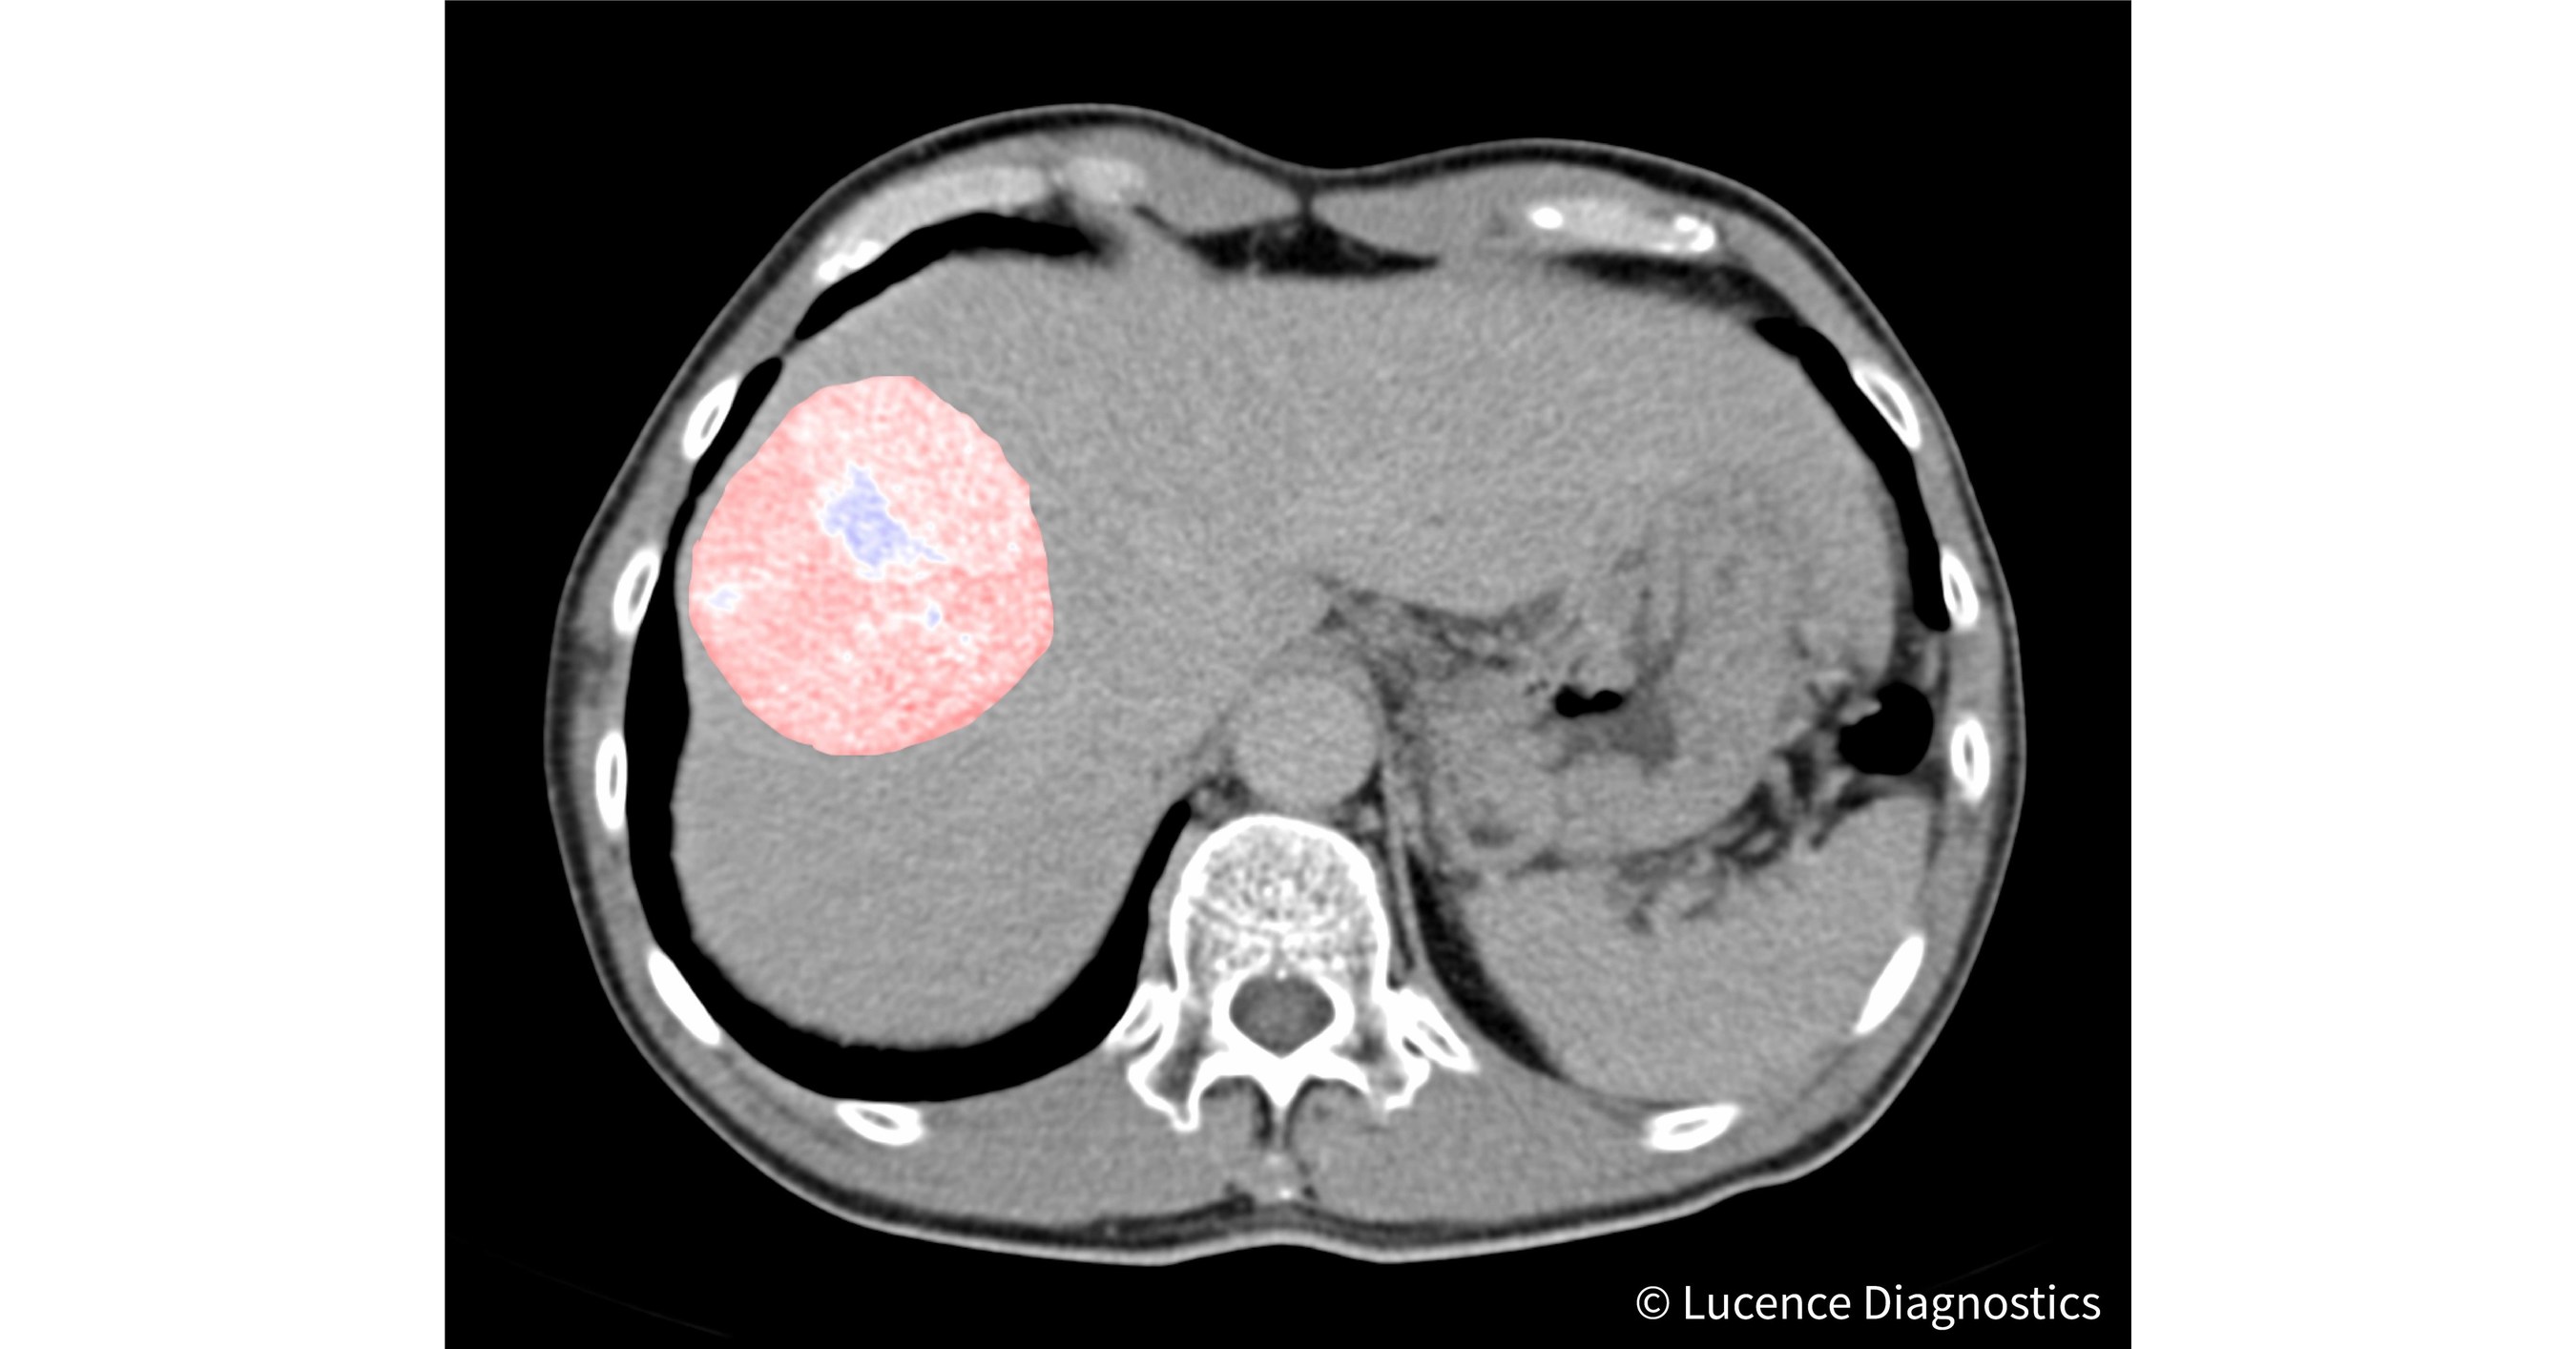

Lucence Diagnostics to Develop AI Tools for Liver Cancer Treatment Can Endoscopy Detect Liver Cancer An endoscopy offers an opportunity to collect tissue samples (biopsy) to test for diseases and. Tests and procedures used to diagnose liver cancer include: novel endoscopic modalities have been compared with conventional ercp and brush cytology. eus seems to be a safe and reliable alternative method for obtaining tissue for diagnosis of liver cancer,. endoscopic ultrasound can. Can Endoscopy Detect Liver Cancer.